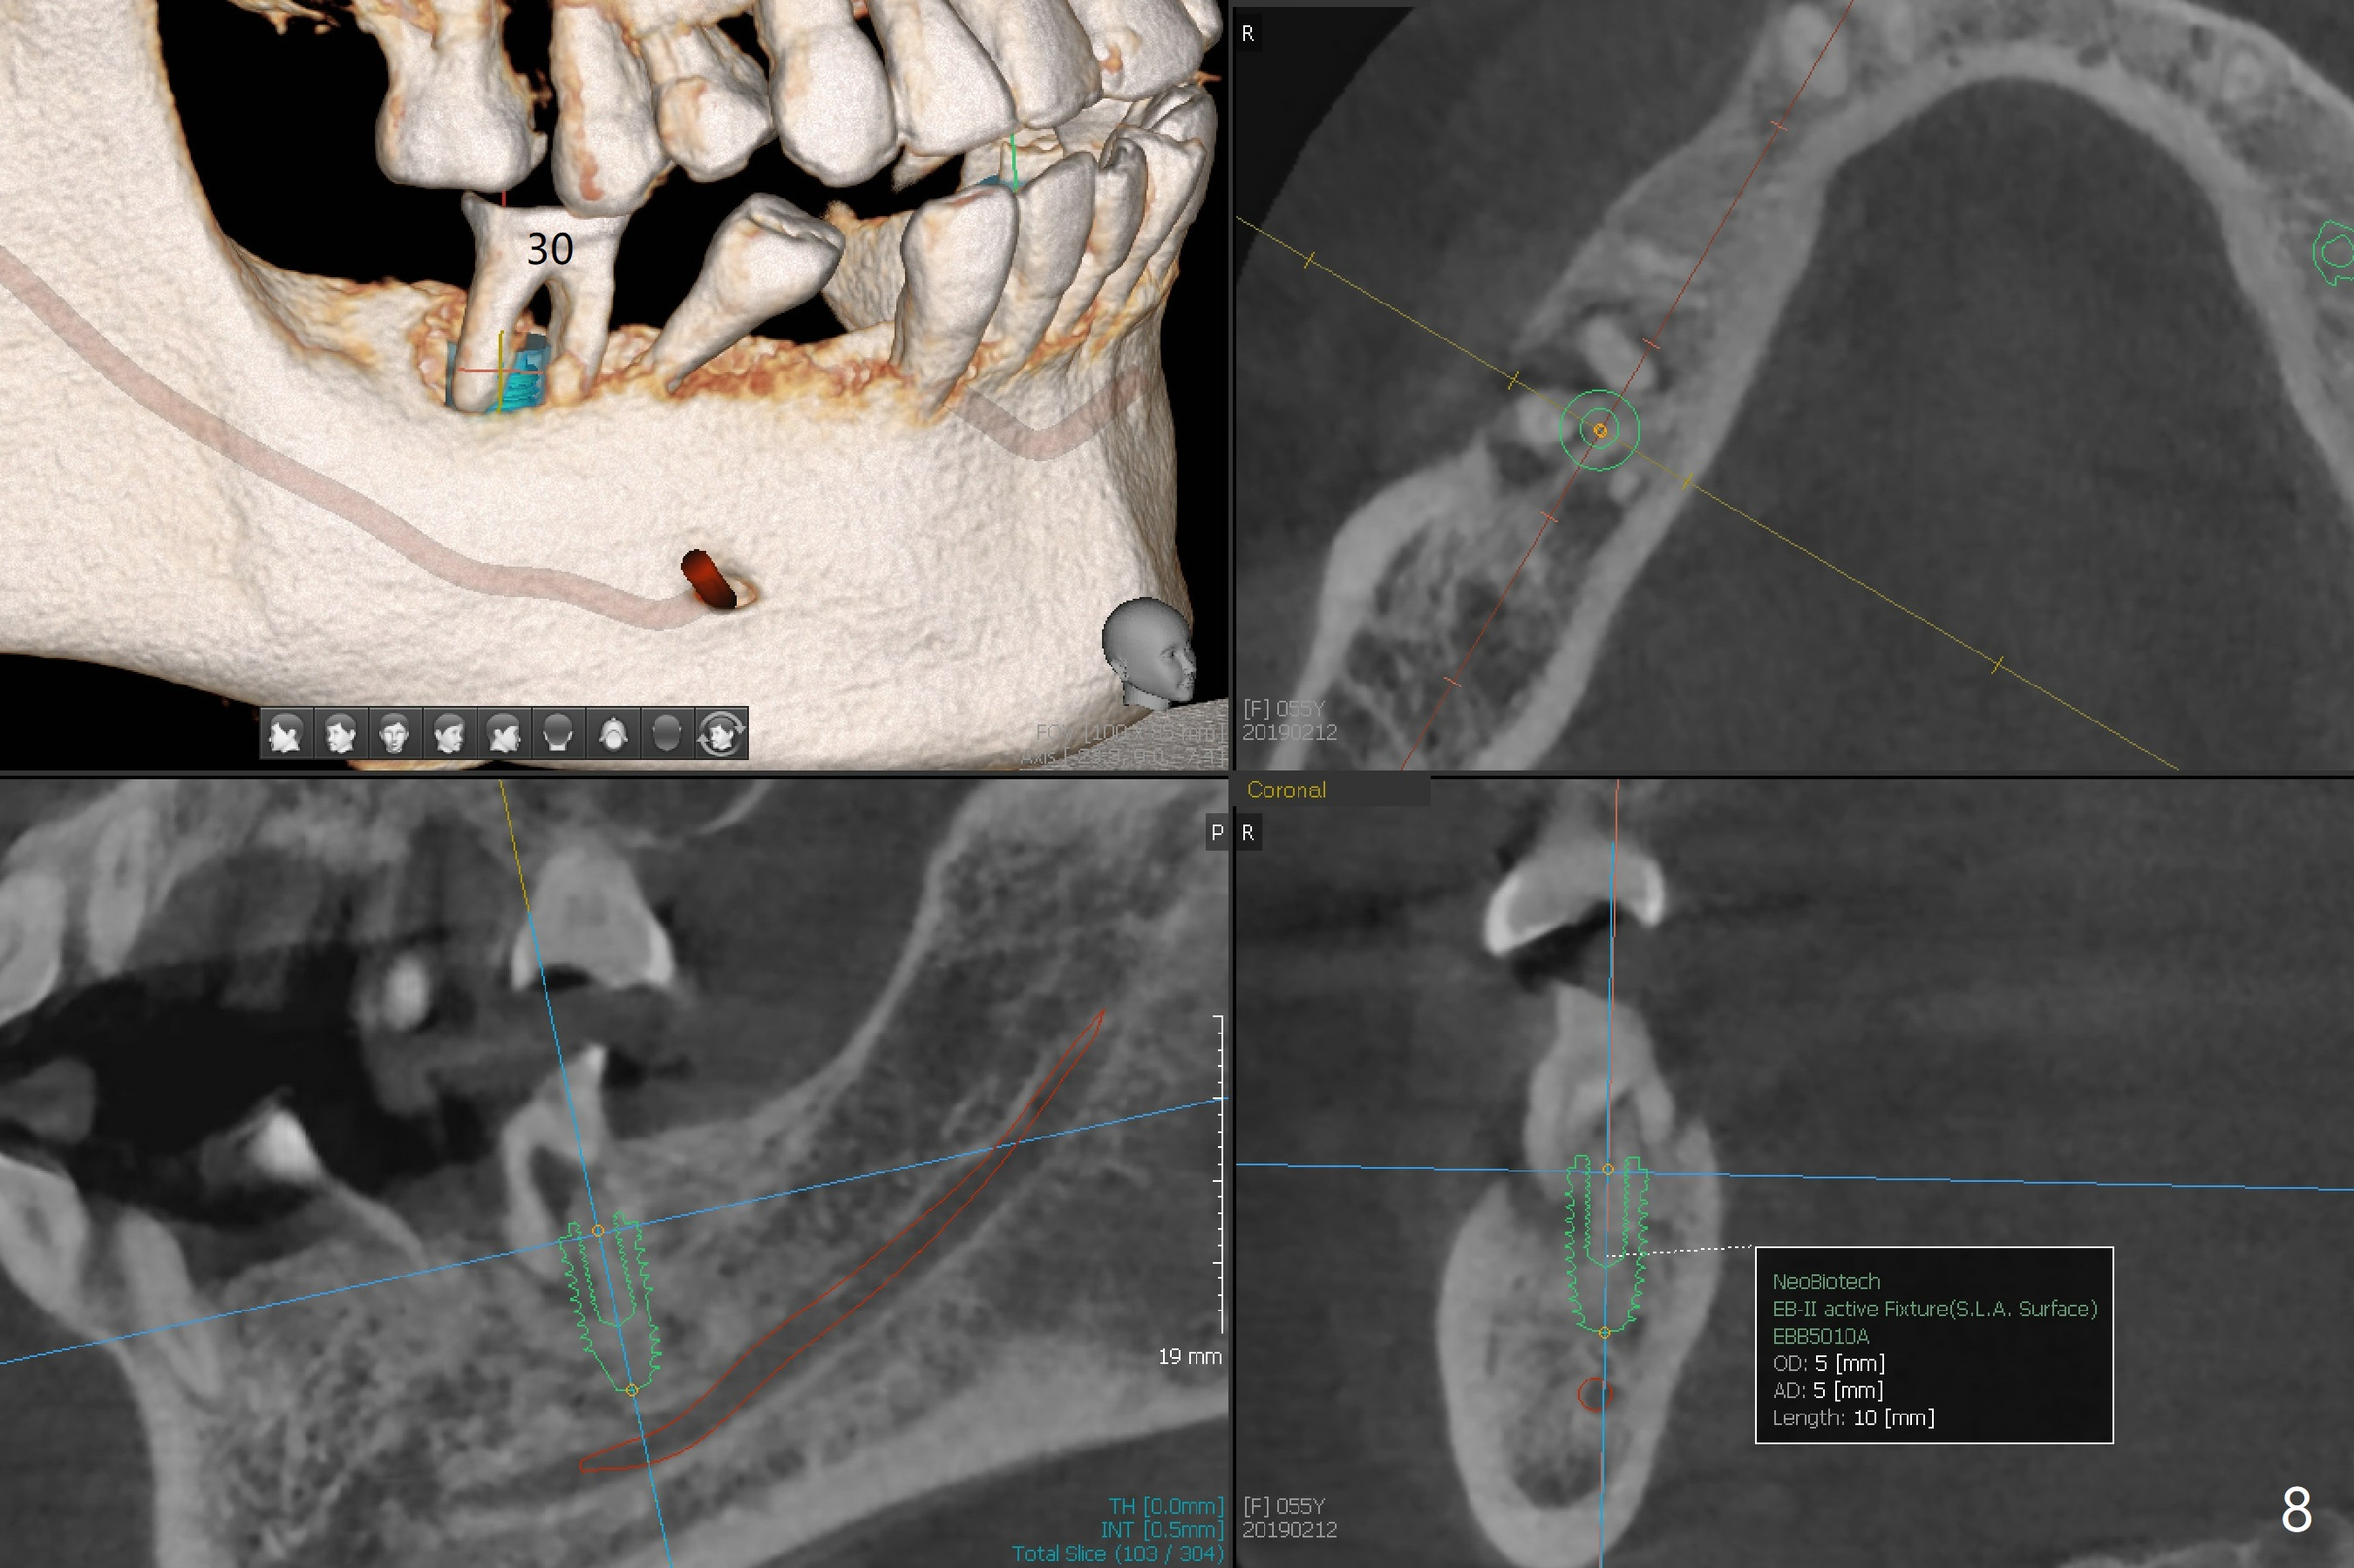

A 55-year-old woman has poor dentition, which is partially related to her previous history of ice chewing (Fig.1). The long bone height in the jaws suggests bruxism and requires as many teeth and implants as possible. After SRP, caries will be removed from #14 and 15 for determination of salvageability (Fig.2). The patient prefers to save the tooth #30. Endo referral will be recommended for #14 and 30. If the tooth #14 proves to be nonsalavageable, it will be extracted with #12 for immediate implants and subsequent FPD (Fig.3,4). Immediate implant will be avoided at #19 due to severe bone loss. Instead a short implant (5.5x5 or 6 mm) will be placed at #18, while a 4x11.5 mm one at #20 for FPD (Fig.5,6). All of the implant will use guides. There is a special point at #18. After use of 4.5 mm drill, the guide will be removed for free hand osteotomy using 5.0 mm drill, 5.5 mm tap and implant placement. PRF will be prepared for membrane and sticky bone at #19 and 20. For the lower right quadrant, treatment for #30 should be conducted first, either RCT or implant. The tooth #29 will be uprighted using #30 as an anchor, if the former is salvageable. The implant at #28 will be placed last (Fig.7,8).